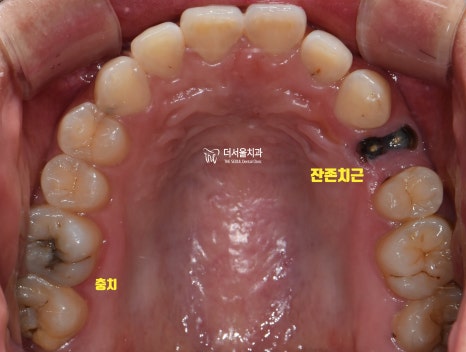

초진 사진을 보면

상실된 치아는 물론이며

잔존 치근, 충치

여러 문제들이 얽히고설켜있었습니다.

자, 좌측 먼저 개선을 돕기로 했습니다.